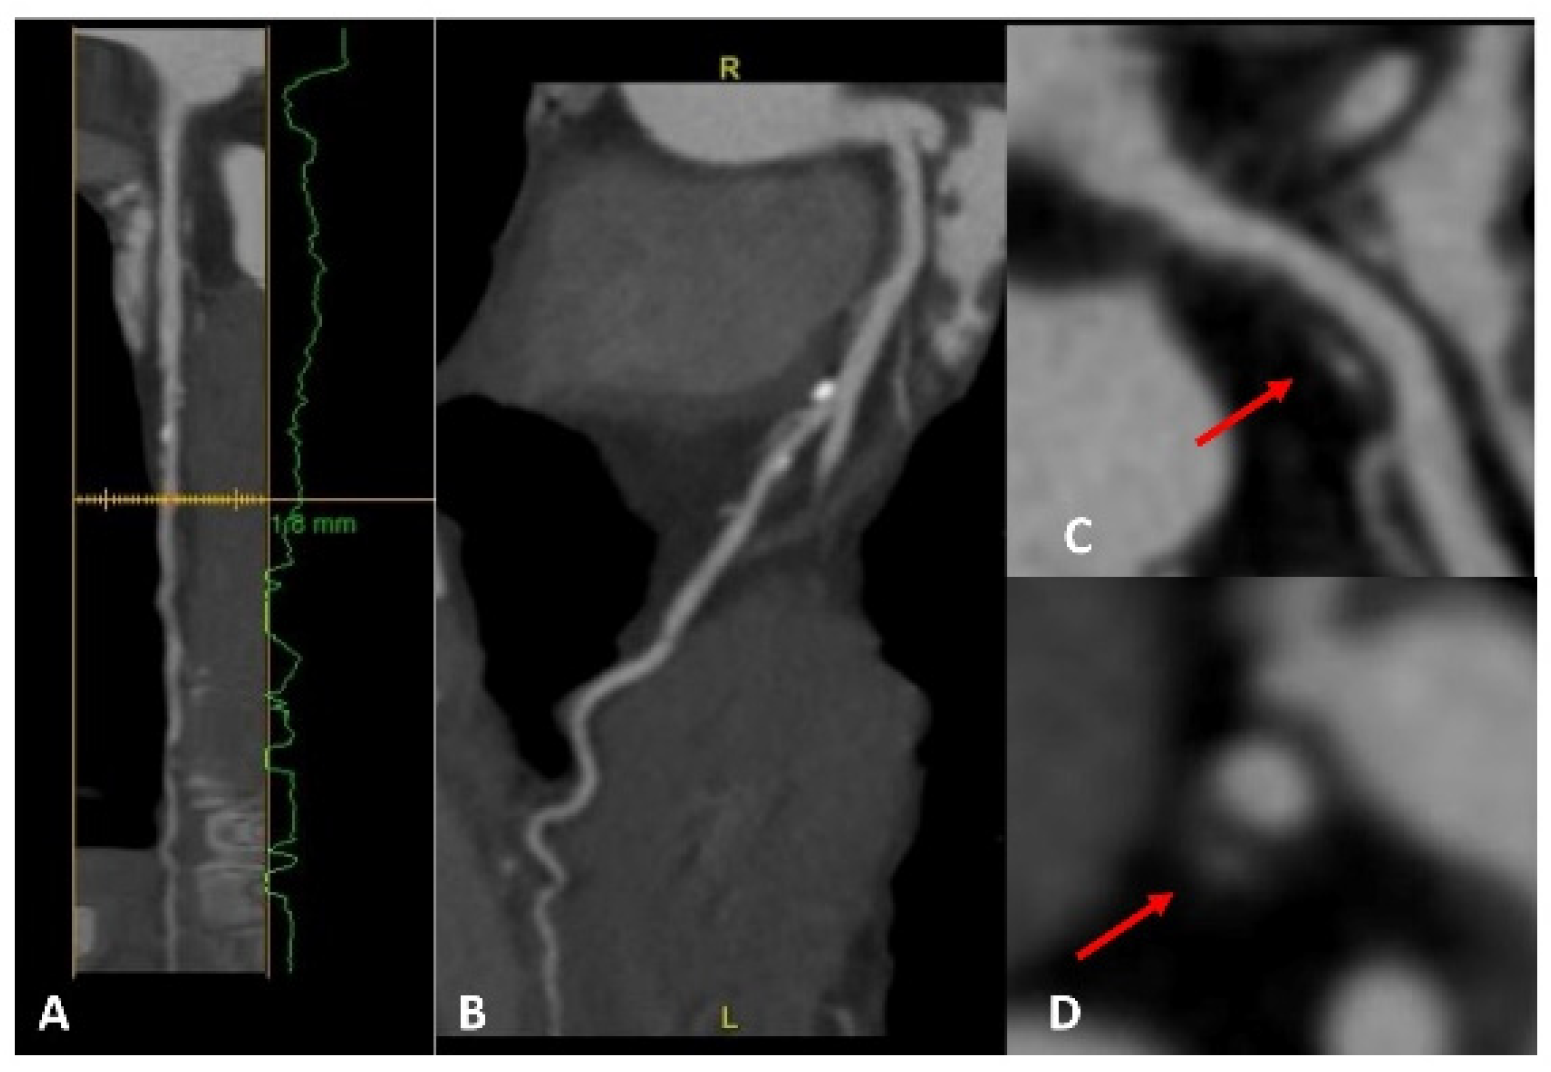

Figure 1.

A patient with a strong family history of CAD, with cardiac CT positive for non-obstructive CAD on proximal LAD (panels A,B). A high-risk fibrolipidic plaque (red arrow) with positive remodeling, low attenuation, and small spotty calcification is evident in both the long (panel C) and short (panel D) axis views.